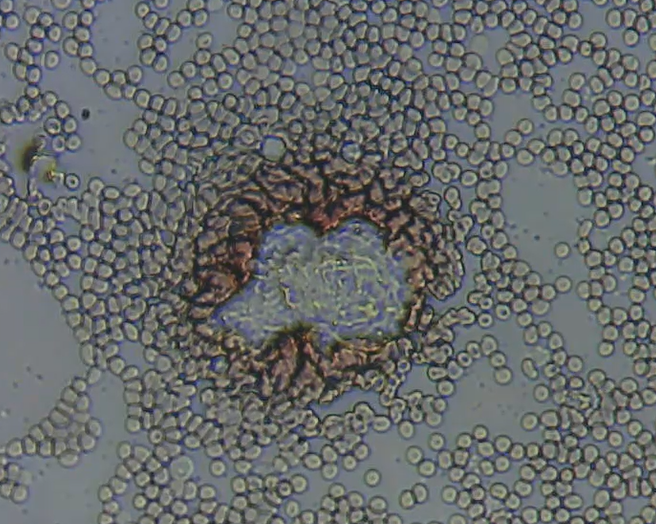

En réalité, les molécules du sang, dans leurs moindres détails, ne sont pas visibles au microscope optique. Seuls le plasma et des amas de molécules, comme le cholestérol, plus ou moins dissous dans le plasma, sont visibles. Les molécules concentrées ou amas observés dans le sang peuvent être des corps étrangers.

Voici un exemple de corps étranger dans le sang : mon image.